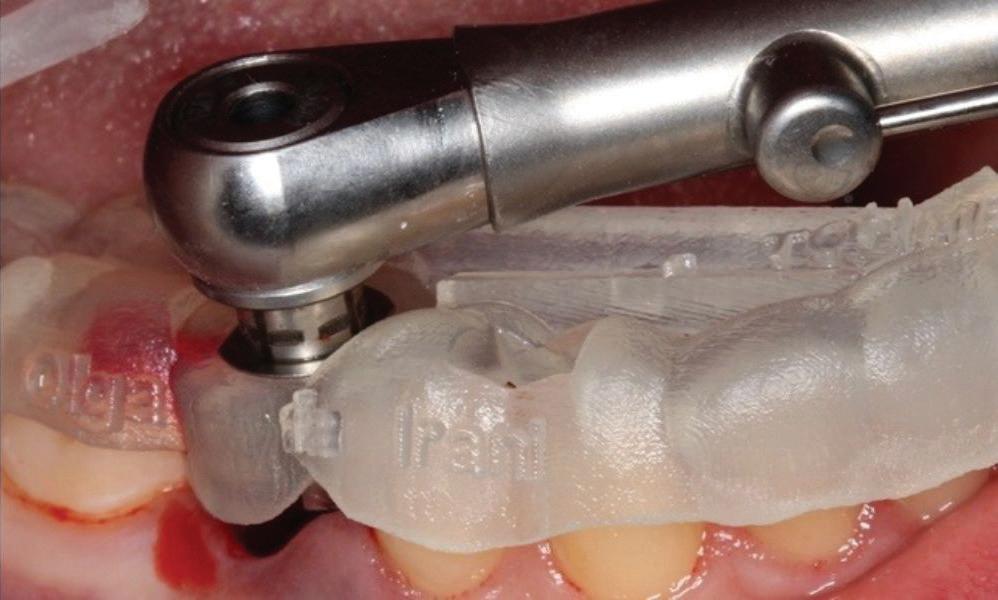

Clear radiographs are essential to accurate diagnosis and are a special test that dentists per form regularly many times throughout the day. Following the ALARA principle, we want to ensure we take a minimal number of radio graphs to ensure low radiation dosage so to repeat radiographs due to operator error should be avoided. The use of film holders allow the clinician to visualise how the radiographs should be taken to optimise the clarity of the image and ensure the diagnostic value of the image. Hawe Solutions x-ray film holders...

Figure 1: Radiographic Image of implants do not demonstrate bone loss due to the bisecting angle of the radiograph taken.

Figure 2: Radiographic image in a paralleling technique of implants dem onstrate moderate peri-implantitis with bone loss that will necessitate treatment.

• Allow exact posi tioning of the film or phosphor plate relative to the tooth - no bending and thus no distortion;

• Require no guesswork - exclusive, automatic reliance on the extraoral aiming and centring device;

• Deliver semi-reproducible images (quasi standardisation)the use of film holders allows some sense of reproducibility for assessment over time; and

• Produce optimally clear radiographs.